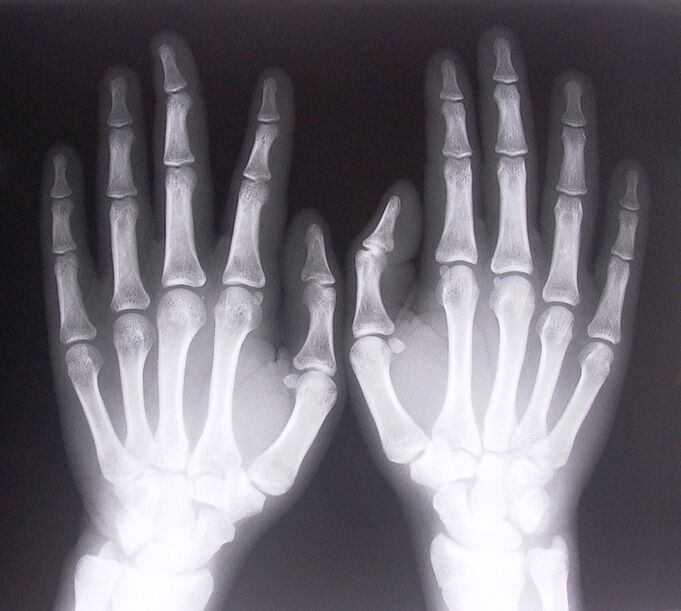

- Stenozli ligamentit. Kasallikning sababini aniqlash uchun rentgen tekshiruvidan o'tish kerak. Semptomlar xarakterlidir: qo'lning og'riqli harakati, siqilgan kaftning ilmog'i. Bundan tashqari, kengaytma paytida odatda chertishlar eshitiladi.

- Rentgen nurlarini oling.